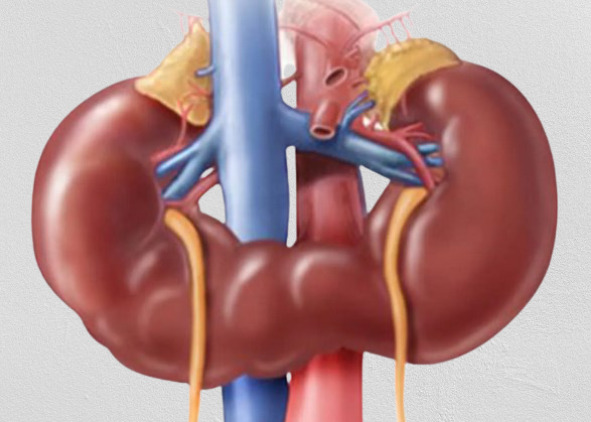

Аномальная каудальная миграция клеточных элементов у плода может приводить к тазовой или подковообразной почкам. Аномальное расположение почек предрасполагает к инфекционным заболеваниям или обструкции мочевого оттока.